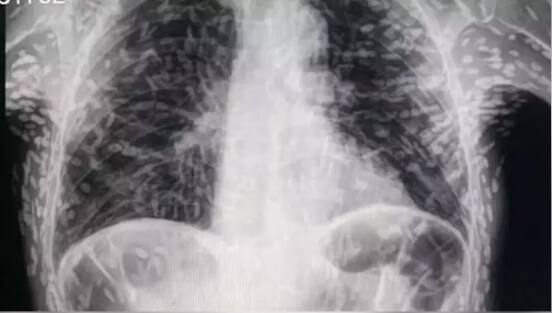

ਮਰੀਜ਼ ਦੇ ਐਕਸਰੇ 'ਚ ਵੱਡਾ ਖੁਲਾਸਾ

ਇੱਕ ਤਾਜ਼ਾ ਮਾਮਲੇ ਵਿੱਚ, ਇੱਕ ਵਿਅਕਤੀ ਜੋ ਖਾਂਘ ਦੇ ਇਲਾਜ ਲਈ ਹਸਪਤਾਲ ਗਿਆ ਸੀ, ਇਹ ਜਾਣ ਕੇ ਹੈਰਾਨ ਰਹਿ ਗਿਆ ਕਿ ਉਸਦੇ ਸਰੀਰ ਵਿੱਚ ਦਰਜਨਾਂ ਟੇਪ ਕੀੜੇ (Tapeworms) ਹਨ। ਹੈਰਾਨ ਕਰਨ ਵਾਲਾ ਖੁਲਾਸਾ ਉਦੋਂ ਹੋਇਆ ਜਦੋਂ ਡਾਕਟਰਾਂ ਨੇ ਮਰੀਜ਼ ਦਾ ਐਕਸਰੇ ਕੀਤਾ। ਸਾਓ ਪੌਲੋ, ਬ੍ਰਾਜ਼ੀਲ ਦੇ ਹਸਪਤਾਲ ਦਾਸ ਕਲੀਨਿਕਸ ਬੋਟੂਕਾਟੂ ਦੇ ਡਾਕਟਰ ਵਿਟਰ ਬੋਰਿਨ ਪੀ. ਡਿਸੂਜ਼ਾ ਦੁਆਰਾ ਟਵਿੱਟਰ 'ਤੇ ਸ਼ੇਅਰ ਕੀਤੇ ਜਾਣ ਤੋਂ ਬਾਅਦ ਸਕੈਨ ਦੀਆਂ ਤਸਵੀਰਾਂ ਵਾਇਰਲ ਨਹੀਂ ਹੋਈਆਂ ਹਨ। ਟੈਸਟਾਂ ਅਤੇ ਸਕੈਨਾਂ ਤੋਂ ਪਤਾ ਚੱਲਿਆ ਹੈ ਕਿ ਉਹ ਵਿਅਕਤੀ ਸਿਸਟੀਸਰੋਸਿਸ ਤੋਂ ਪੀੜਤ ਸੀ।